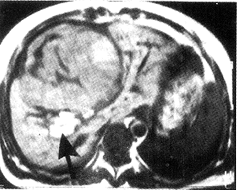

2.CT表现:平扫病变呈分叶状,低于肝实质密度,边缘清楚。4例可见较多脂肪成分,分布在肿块周边。1例于薄层扫描(3 mm)显示点状脂肪密度,1例未显示脂肪成分。增强扫描:动脉为主期(早期)肿块呈明显强化,4例与主动脉密度近似,于注药2~4分钟后转变为低于肝实质密度(图2);2例延迟10~15分钟后病变呈等密度(与血管瘤相似)。6例均无肝硬化表现。术前2例因肿块内脂肪成分多而考虑为HAML,2例诊断为血管瘤,2例诊断为肝癌。

图2 肝增强CT扫描延迟相,肿瘤密度低于肝实质密度,后部有脂肪成分